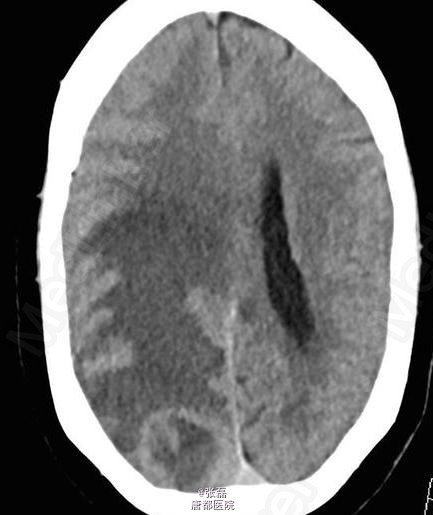

颅脑平扫 CT 显示右侧枕叶肿块,其内密度不均,中间呈低密度。周围脑组织呈血管源性水肿性低密度,邻近脑沟、裂变窄变浅,右侧侧脑室受压变形。 颅脑平扫加强化 MRI 显示:右侧枕叶见一长 T1 等长 T2 异常信号,FLAIR 呈高信号,注入对比剂后呈明显不均质强化,中间呈坏死性不强化改变。病变强化后边界不清,邻近脑实质和后方软脑膜受侵。病变定位脑内,非硬脑膜起源,未见脑膜尾征。周围脑组织可见血管源性水肿征象,累及皮层下和深部白质。MRI 显示较 CT 清晰、明显。 病理诊断:脑转移瘤